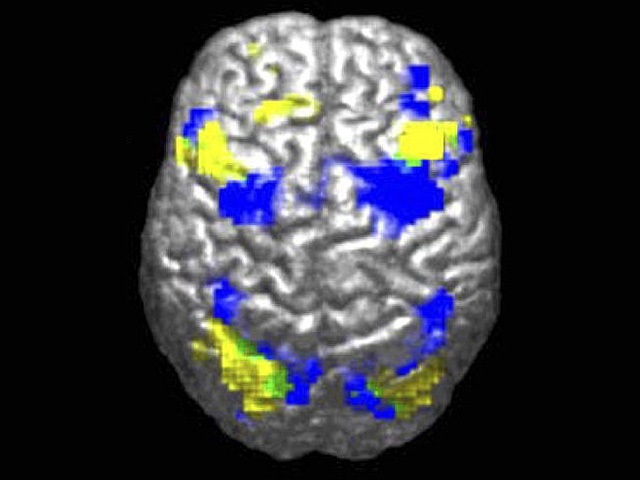

Новая модель ИИ может расшифровывать МРТ головного мозга за секунды

ИИ-модель анализирует снимки мозга за секунды, помогая быстрее обнаруживать заболевания и распознавать экстренные состояния.

По данным исследования, ученые из Мичиганского…